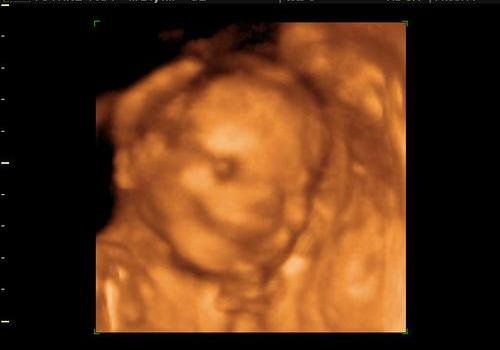

Én úgy tudom, ha kislányt mondanak UH-n, az biztosabb. A kisfiú csak akkor, ha tutira az látszik. Egy 4D UH-n sokkal biztosabbra meg tudják mondani (persze ott is csak akkor, ha nem takargatja).

Nem ciki, ha nem látod, mit kéne látnod. Kérj róla videó vagy DVD felvételt (mozgóképet). Nézd meg 50-szer és látni fogsz mindent. A 2. terhességnél meg már akár magadnak is csinálhatod

. (Én a másodiknál azt is megláttam, amit nem akartam. Egy pillanatra áthúzta a vizsgálófejet a doki azon a bizonyos részen (amit mi nem akartunk tudni) és itthon mégis felfedeztem

. Azóta nem is nézek UH-t, csak ha biztos nem nézi azt a részt, mert tuti meglátnám!:) (Jó, nem a 12 hetesen, de mondjuk a 28 hetesen már biztosan, ha nem takargatja magát.))